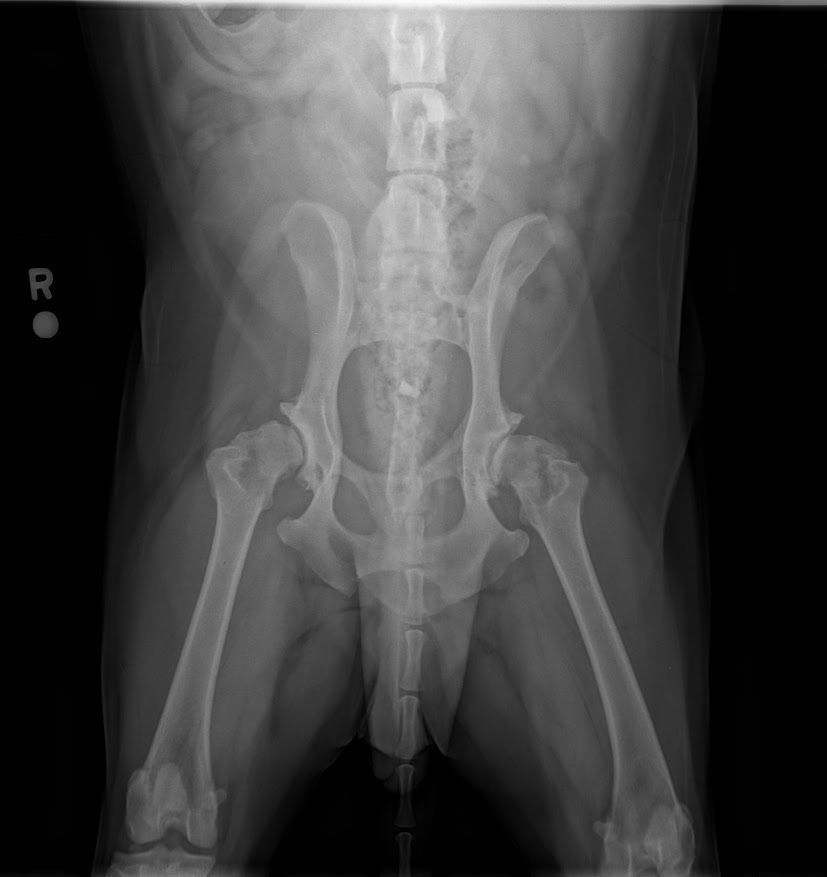

- Advanced diagnostic imaging

Recognizing and Addressing Osteoarthritis in Pets

Osteoarthritis is a common condition that affects many pets, especially as they age. It's crucial to be aware of the signs and seek timely intervention. Here are some reasons why your pet may need osteoarthritis care:

Early detection and management of osteoarthritis can significantly improve your pet's comfort and mobility. Our experienced veterinary team at Allure Veterinary Hospital & Urgent Care is equipped to provide tailored care for your pet's specific needs.